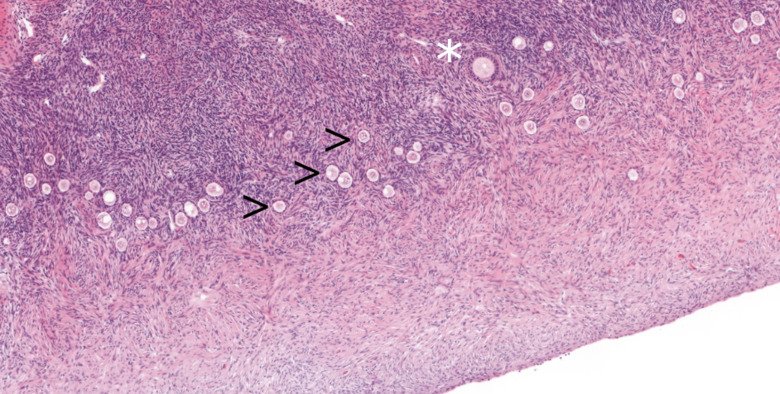

Vissa medicinska behandlingar, som kemoterapi, kan rädda livet men samtidigt skada äggstockarna och fertiliteten. För att möjliggöra framtida möjligheter att bli med barn kan äggceller eller äggstocksvävnad frysas innan behandlingen påbörjas. För barn, som inte ännu gått igenom puberteten, är nedfrysning av äggstocksvävnad det enda alternativet. Metoden är välbeprövat för vuxna kvinnor, men mindre studerat hos barn. Vi har initierat en nationell studie, Sveafertil, där flickor och unga kvinnor med mycket hög risk för infertilitet till följd av sina behandlingar kan frysa ned en del av äggstocken och donera en liten del för vår forskning. Vårt mål är att jämföra äggstocksvävnad från barn med vuxen vävnad i detalj samt identifiera molekyler och celler som påverkas av kemoterapi och med denna kunskap förfina metoderna för de yngsta patienterna. Läs mer om projektet här.

Impact of first-line cancer treatment on the follicle quality in cryopreserved ovarian samples from girls and young women.

Pampanini V, Wagner M, Asadi-Azarbaijani B, Oskam IC, Sheikhi M, Sjödin MOD, Lindberg J, Hovatta O, Sahlin L, Björvang RD, Otala M, Damdimopoulou P, Jahnukainen K

Hum Reprod 2019 Sep;34(9):1674-1685

Detaljerad cellulär karta av äggstocken genom livet

För att kunna studera hur miljöexponeringar och medicinska behandlingar påverkar äggstocken måste vi förstå dess funktion på en cellulär och molekylär nivå. Ett av våra forskningsmål är därför att identifiera olika celltyper inom äggstocken och studera hur dessa förändras genom livet. Äggstocken genomgår förändringar, t ex under puberteten, men påverkan på de minsta folliklarna, som innehåller omogna ägg, är inte väl undersökt. Vi analyserar äggstocksprover från flickor, unga tjejer och vuxna kvinnor för att skapa en omfattande bild av äggstockens utveckling och funktion från barndom, genom puberteten, till vuxen ålder.

För att kunna avgöra om miljöexponeringar direkt påverkar äggstocken, genomför vi kontrollerade exponeringsexperiment i laboratoriet. Vi exponerar äggstocksvävnad och celler i odling för kemikalier som vi har identifierat i våra populationsstudier om kemikalier och kvinnlig fertilitet. Vi undersöker om de exponerade folliklarna växer normalt och vilka gener som påverkas. Våra resultat visar hur och genom vilka molekylära mekanismer äggstocksfunktion kan påverkas av miljöfaktorer. Denna information kan användas för att bättre förstå samband mellan exponering och nedsatt fertilitet hos kvinnor, samt för att utveckla tester för att utvärdera kemikaliers reproduktiva toxicitet.